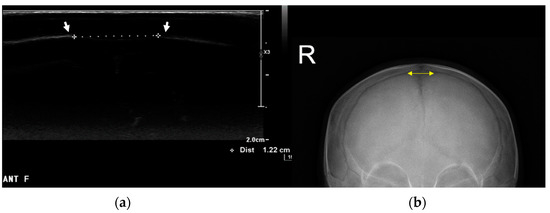

Ultrasonographic Measurement of Anterior Fontanelle Size in Infants with Deformational Plagiocephaly

Background/Objectives: We aimed to investigate the relationship between deformational plagiocephaly (DP) severity and anterior fontanelle size and to explore the connection between fontanelle size and developmental delay. Methods: We enrolled 189 (122 boys and 67 girls; mean corrected age, 119.79 days) [...] Read more.

Background/Objectives: We aimed to investigate the relationship between deformational plagiocephaly (DP) severity and anterior fontanelle size and to explore the connection between fontanelle size and developmental delay. Methods: We enrolled 189 (122 boys and 67 girls; mean corrected age, 119.79 days) of the 256 infants who visited our clinic for plagiocephaly between March 2022 and June 2023. This study analyzed the correlation between cranial vault asymmetry (CVA) and anterior fontanelle size as measured using skull anteroposterior (AP) radiography and ultrasonography. The severity of DP was graded from minimal to severe based on the Argenta classification. Infants were grouped according to CVA severity as follows: Group 1 (CVA ≤ 5 mm), Group 2 (5 mm < CVA < 10 mm), and Group 3 (CVA ≥ 10 mm). Additionally, 40 infants underwent the Denver Developmental Screening Test II (DDST-II) for neurodevelopmental delays and were divided into groups based on the presence or absence of developmental delays for fontanelle size comparison. Results: Age showed a significant negative correlation with fontanelle size (correlation coefficient −0.234, p < 0.05), indicating that fontanelle size decreases as infants age. No significant differences in fontanelle size were observed among the three CVA groups (p = 0.074) or between the developmentally delayed and non-delayed groups (p = 0.09). This study found no correlation between CVA and fontanelle size or between fontanelle size and developmental delay. Conclusions: The findings show that, while anterior fontanelle size decreased with age, there was no significant correlation between the fontanelle size and the severity of deformational plagiocephaly or developmental delays. Full article